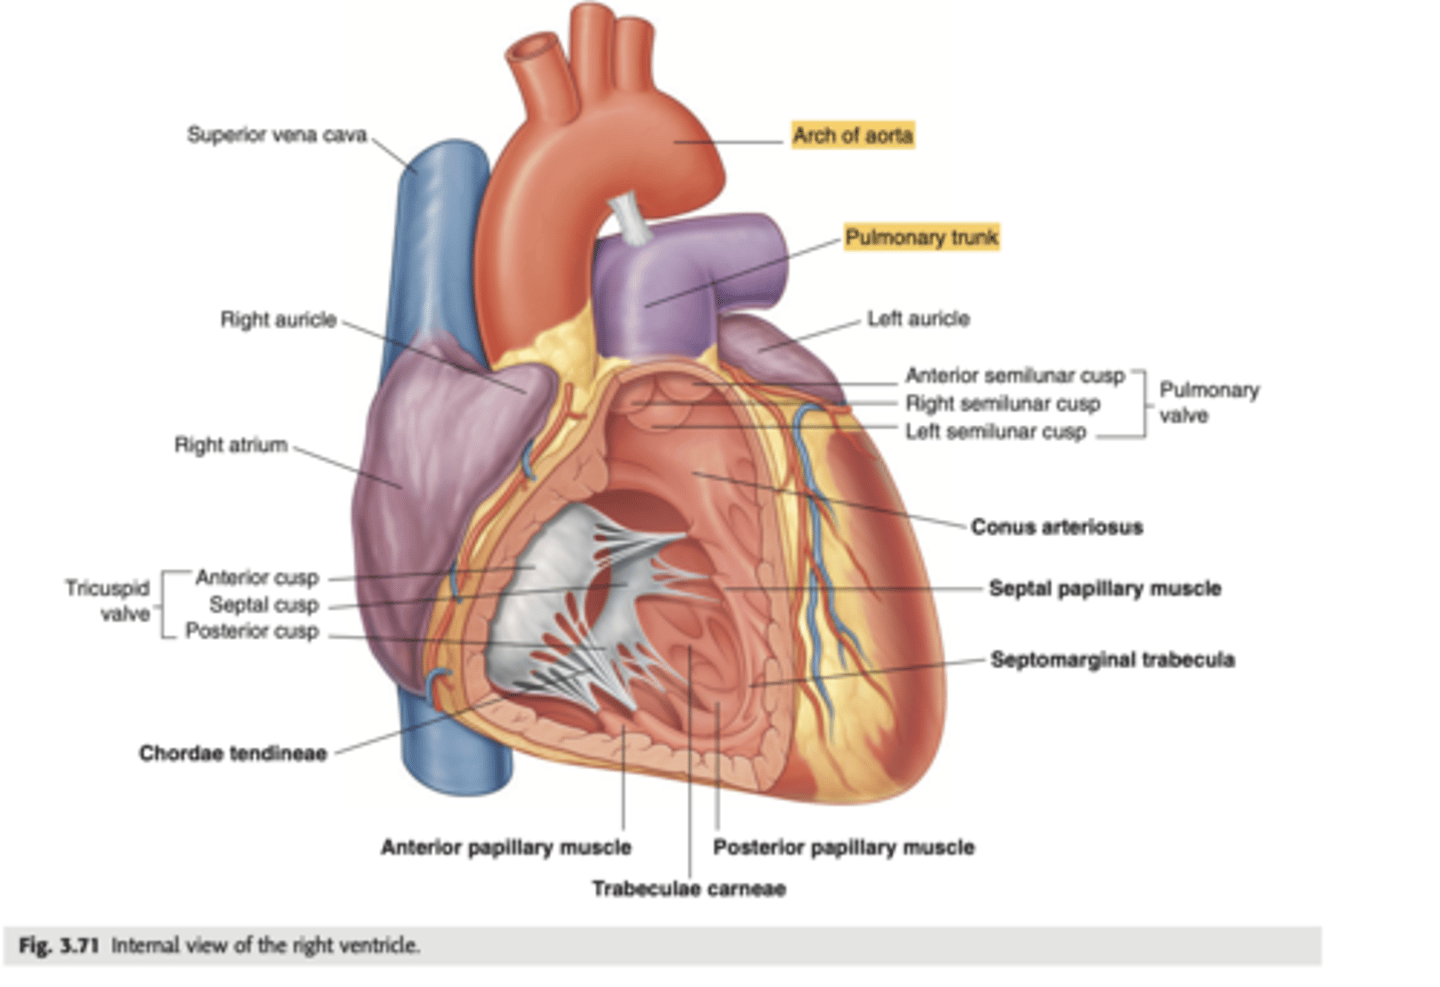

What are the walls of the right ventricle?

. Anterior wall

. Posterior wall

. Septal wall

Right ventricle has a conical shape with 2 o 3 walls

Describe the two portions of the medial/septal face/wall of the right ventricle.

infundibulum or outflow region or conus arteriosus (smooth and membranous)

trabeculae carnae (muscular and irregular)

What are the 3 cusps of the tricuspid valve?

Anterior

Posterior

Septal

What connect the cusps of the valve a to papillary muscles in the

right ventricle?

Chordae tendinae

With the contraction of the walls of the ventricle what's the action of the papillary muscles?

contract as well

With the contraction of papillary muscles what will be happen with the valve?

Close

What is the septomarginal trabeculae (or moderator band)?

Part of the conduction system of the heart.

electrical waves pass through this band to reach the papillary muscles.

LANDMARK

What are the positions of the pulmonary valve cusps?

Anterior

Right

Left

What are the 3 parts of the pulmonary valve?

. Nodules. (little point at the center)

. Lunules (from the nodule to the wall)

. Sinus (left in between)